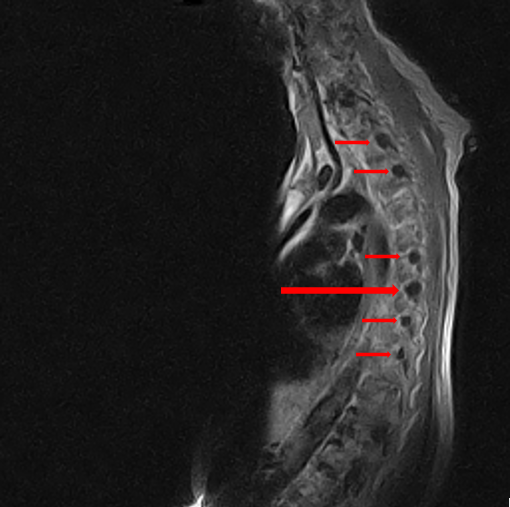

Thoracic MRI reveals multiple perineural cysts (Tarlov cysts) throughout the region with the largest at T10/T11 on the right. Similar findings are present in the cervical and lumbosacral region. These cysts have resulted in pressure remodeling and enlargement of the IVFs.